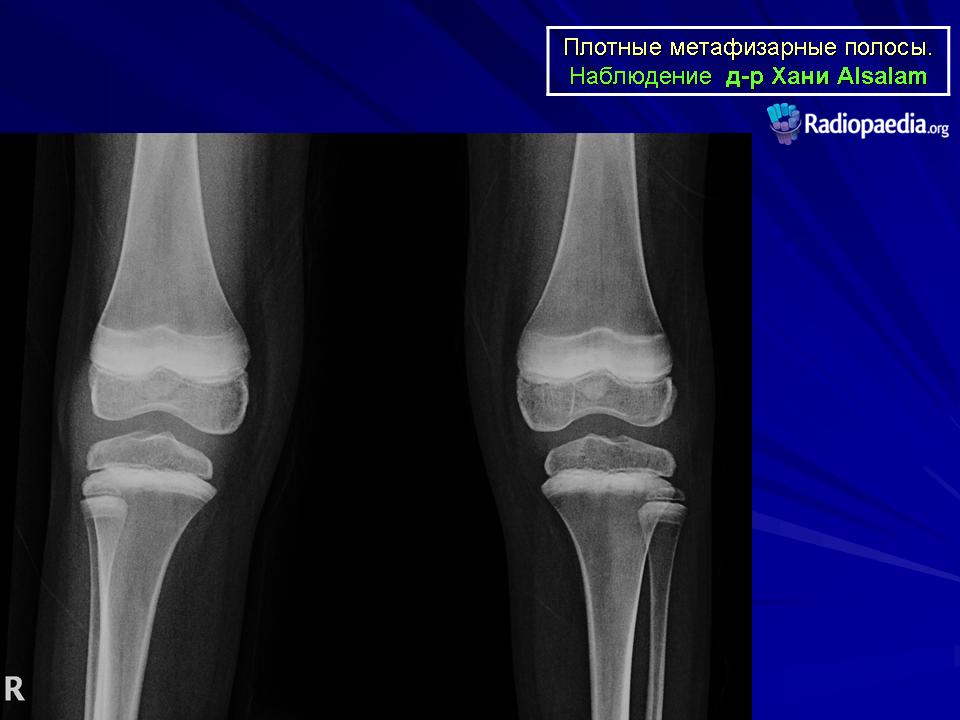

Рентгенологические проявления свинцовой интоксикации в скелете ребенка весьма постоянно, во всех клинически подтвержденных случаях свинцового отравления Фогт находил изменения в рентгенологической картине костей. Во всяком случае положительные рентгенологические данные не только скрепляют в сомнительном случае клинический диагноз, но нередко наводят клинициста на правильный путь и поэтому делаются одним из важнейших элементов устанавливающей диагностики свинцового отравления вообще. Основной рентгенологический признак - это появление полосы затемнения в метафизарном конце кости, другими словами, расширение и значительное повышение интенсивности зоны пре-параторного обызвествления. Чрезвычайно глубокая тень этой "свинцовой полосы" объясняется не только высоким атомным номером и, следовательно, контрастностью самого свинца, но и гистологически доказанным остеосклерозом губчатой трабекулярной метафизарной сети.

Ширина и интенсивность поперечной метафизарной ленты дают известное представление о длительности отравления и о количестве поглощенного свинца. Так, например, узкая, но интенсивная полоска говорит о краткосрочном отравлении концентрированной дозой; наоборот,, широкая, неинтенсивная лента - о длительном действии небольших количеств яда. Разумеется, при этом ширина полоски пропорциональна и скорости роста, и поэтому в различных отделах скелета при общем действии на него свинца "свинцовая полоска" отличается своей шириной. Сильнее всего у ребенка поражаются передние концы средних шести ребер, дистальный конец костей предплечья, оба конца костей голени, дисталь-ный конец бедра и т. д. Все эти данные могут быть использованы для рентгенологической оценки сравнительной скорости роста различных отделов скелета в различные периоды жизни. Лучшим объектом для рентгенологического исследования и здесь служат лучезапястный сустав и голень с коленным суставом. Поперечные ленты иногда не равномерны, а исчерчены рядом полосок различной ширины и интенсивности - это говорит о перемежающемся характере интоксикации. Контуры свинцовой зоны в сторону диафиза могут быть смазаны, т. е. зона постепенно переходит в нормальную структуру. Нередко расширяется и затемняется каемка эпифизарных ядер окостенения. Надкостница не вовлекается в процесс. При прекращении поступления в организм свинца и излечении отравления постепенно рассасывается и "свинцовая полоска".